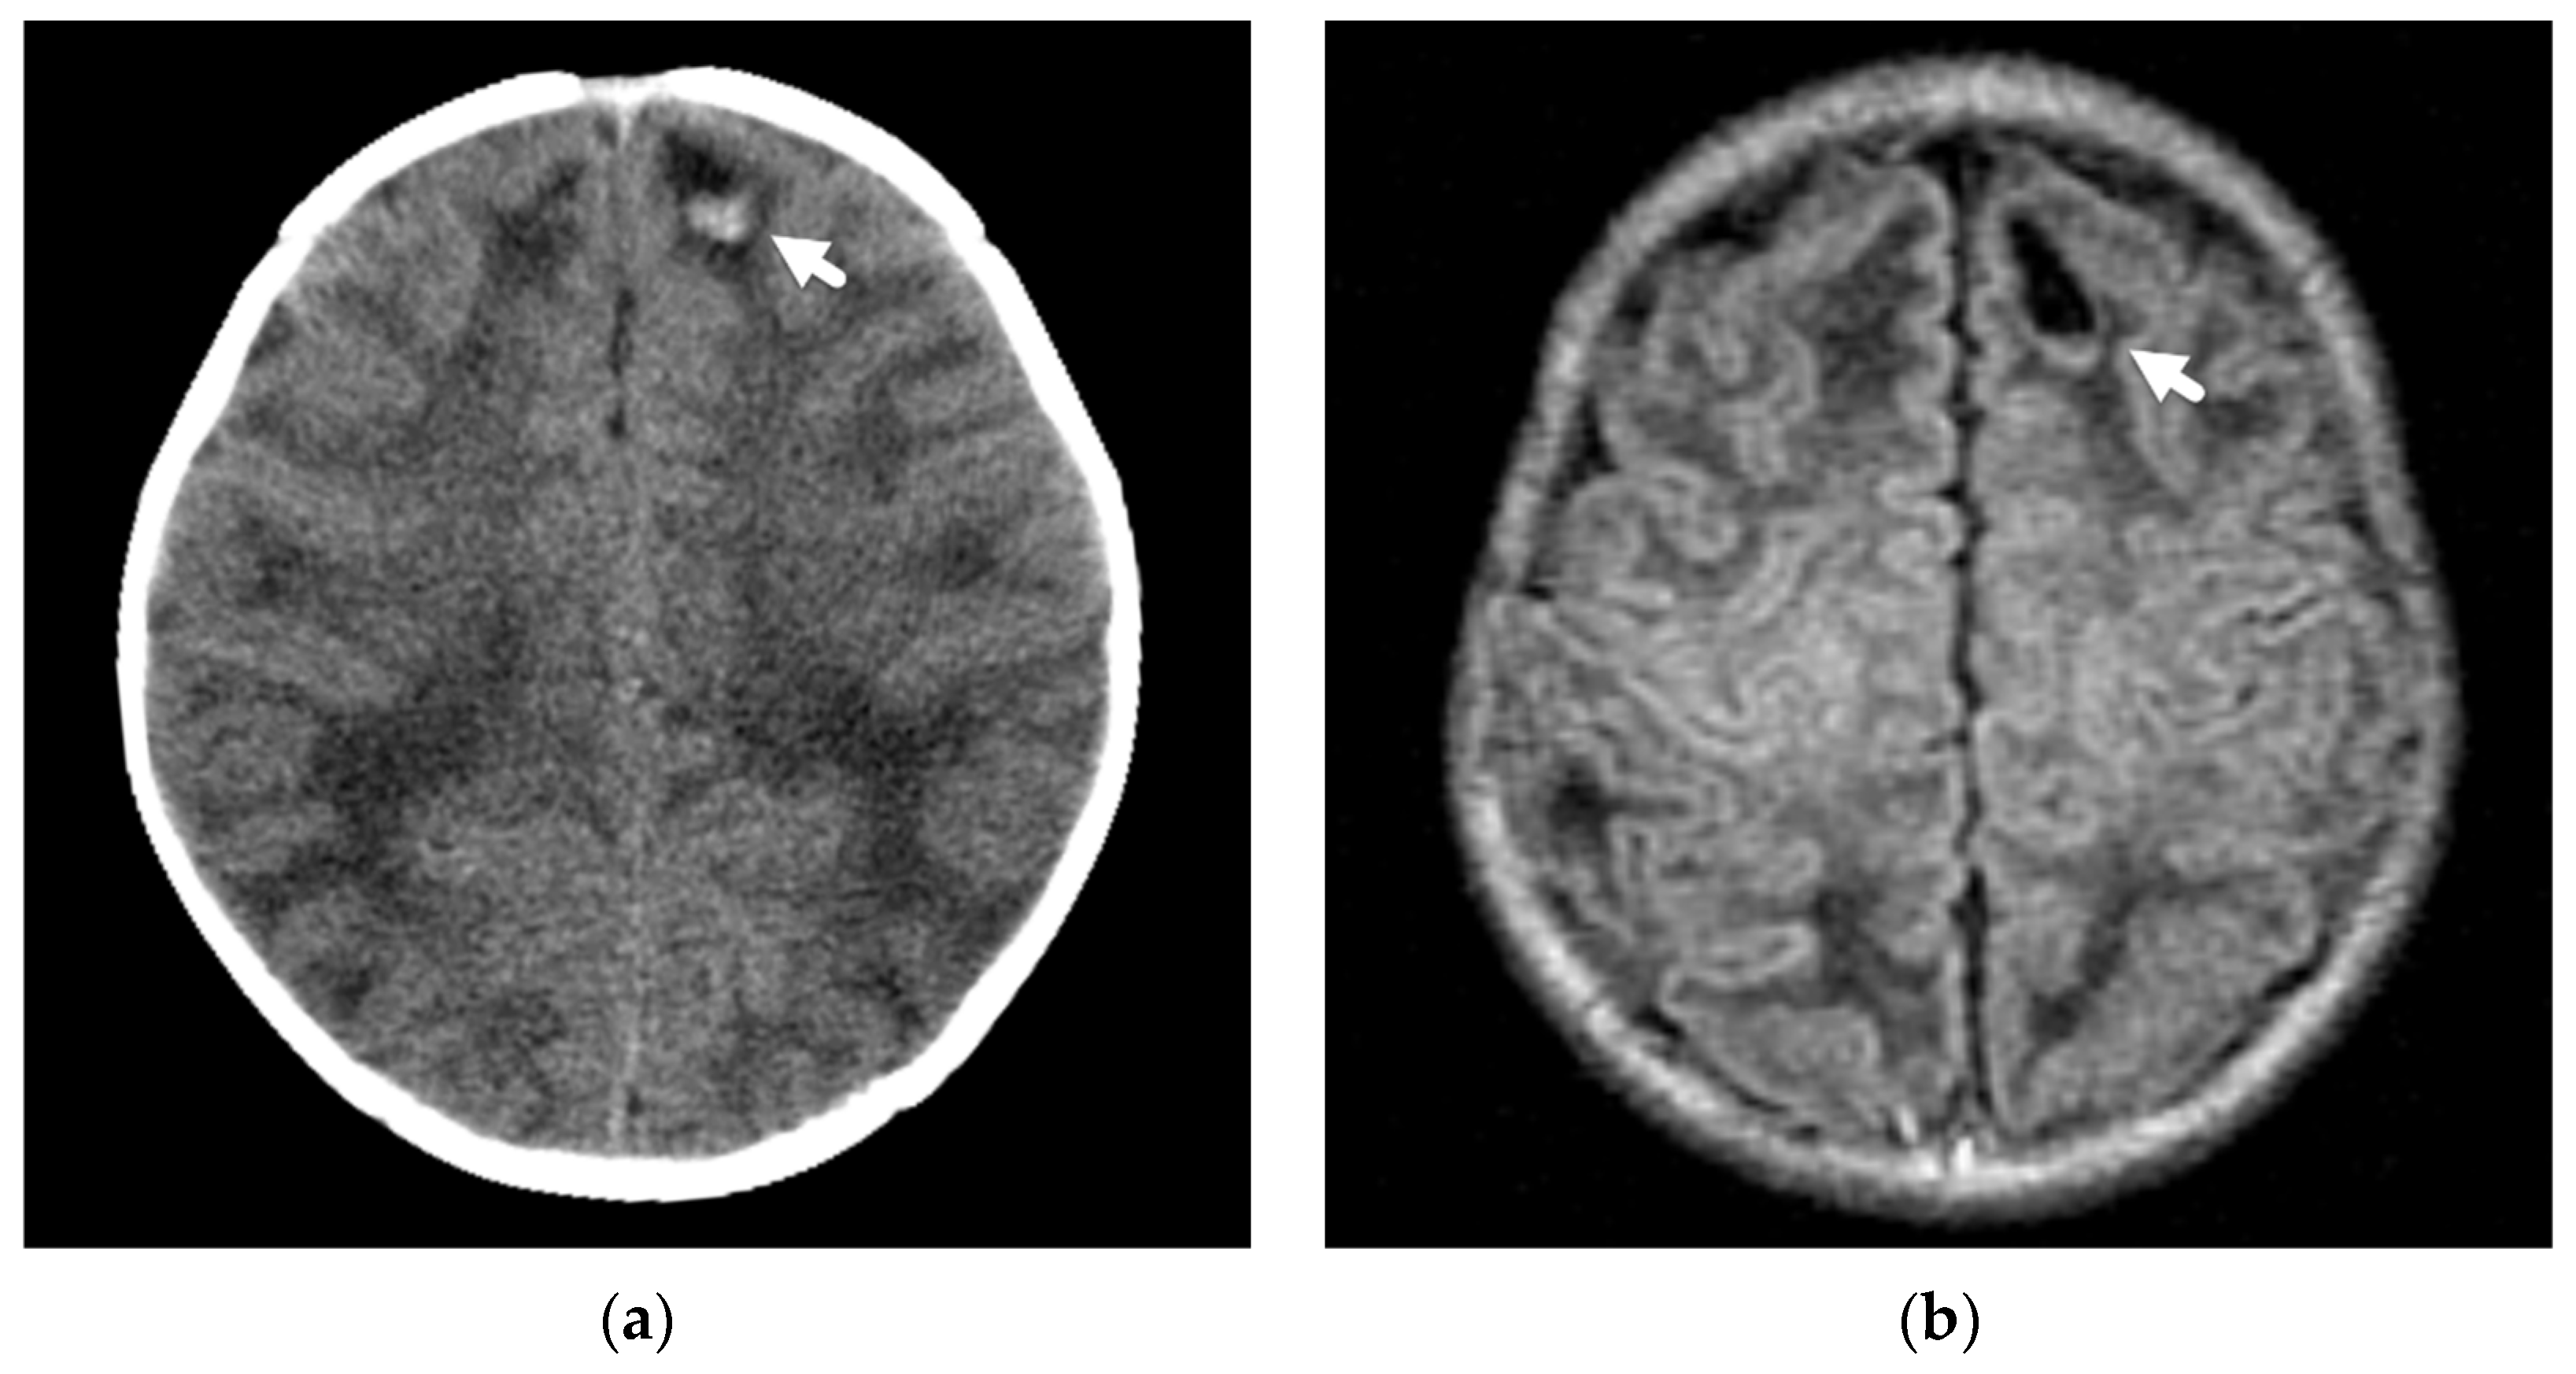

Axonal injuries may be very subtle on CT imaging but may appear as multiple, punctate, low-attenuation foci or petechial hemorrhages, usually involving hemispheric white matter, the corpus callosum, cerebellum, and brainstem. Deep subarachnoid hemorrhage and brain swelling may be seen as associated findings on both CT and MRI. Susceptibility-weighted imaging is a key MR sequence for detecting the punctate hemorrhagic foci, and diffusion-weighted imaging aids in the detection of non-hemorrhagic, traumatic axonal injury Figure 4.

Figure 4.

Axonal injury and lacerations/contusional tears in a 4-month-old male presenting with seizure and lethargy. (a) Initial axial CT image demonstrates right parafalcine high-attenuation subdural hemorrhage (white arrow); (b) coronal reconstruction in bone algorithm demonstrates a right parietal bone fracture (black arrow) with overlying soft tissue swelling (white arrowhead); (c) axial T2-weighted MR image on day 4 demonstrates bilateral lacerations/contusional tears with fluid-hemorrhagic levels near the temporal-occipital lobe junctions (white arrows); (d) axial susceptibility-weighted image demonstrates layering hemorrhage in lacerations/contusional tears (white arrows) and axonal injury near the cortical-white matter junction in each frontal lobe (black arrows).

Traumatic head injury may also result directly in parenchymal contusions and lacerations. These injuries are also less commonly observed in abusive head trauma [24,25,26,28] but, when present, are frequently seen in conjunction with other traumatic injuries, such as overlying extra-axial hemorrhage or fractures (Figure 5). Given their more focal nature, these insults typically result in more localized neurologic deficits instead of a diffuse encephalopathy, although they certainly can be seen in conjunction with more diffuse injuries. In Zimmerman et al.’s review of DWI in abusive head trauma [25], parenchymal contusions were one of the least frequent patterns of described parenchymal injury, occurring in only 2/33 cases, potentially reflecting different mechanisms of injury in the abusive head injury population as opposed to a direct cranial insult from an accident, such as when a child accidentally falls from a second-story window. Other studies have also demonstrated the more infrequent occurrence of contusions in this population [24,27]. Contusions more commonly affect older children, are often multiple, maybe hemorrhagic or non-hemorrhagic, and are usually centered near the surface of the frontal and temporal lobes near the adjacent bone surfaces and dural reflections. Multiplanar CT reconstructions will allow increased detection of subtle contusions in the inferior frontal and anterior temporal lobes. On MRI, gradient echo or susceptibility-weighted imaging will aid in detection of more subtle hemorrhagic contusions, while non-hemorrhagic contusions may be more readily detected on diffusion-weighted imaging along the surface of the brain. Contusions often increase in size over the first few days as well as develop surrounding edema.

Slit-like lacerations or tears/clefts at the cortical-white matter junction, mainly in the frontal and anterior temporal lobes, have been described in young infants as a result of trauma. On imaging, these lesions may appear as focal cerebrospinal fluid-like clefts or lesions with layering fluid–fluid levels or layering hemorrhage [47,49,50] (Figure 6). Palifka et al. [50] described these focal lacerations in 18/137 abusive head injury patients of less than 3 years of age, with almost 90% (16/18) occurring in patients less than 1 year of age. However, none were demonstrated in a comparison cohort of patients with moderate to severe accidental head injury (n = 28 with 8 less than 1 year of age), including those that sustained injuries from falls, motor vehicle collisions, and young pedestrians hit by automobiles. In their series, the lacerations or tears were detected on noncontrast CT in 9/18 cases as linear or fluid/hemorrhagic attenuation clefts in the subcortical white matter in the supratentorial brain, with sixty percent (11/18) demonstrating associated fractures or regional scalp swelling. MR imaging demonstrated a linear cleft or focal fluid-fluid level or hemorrhagic level in the subcortical white matter and in over half, was best demonstrated on gradient echo or susceptibility-weighted sequences. In 2/18 patients, however, these lacerations were most easily detected on DWI. Lesions most commonly occurred in the frontal lobes, and although some were isolated, seven patients had multiple lacerations. In most cases, other traumatic lesions, including retinal and extra-axial hemorrhages or injuries to other extracranial locations, were detected either clinically or on imaging.

Figure 6.

Focal laceration or contusional tear in a 2-month-old former preterm male infant presenting with seizure. (a) Initial axial noncontrast CT demonstrates a small, focal, left frontal lobe laceration/tear with layering posterior hemorrhage (white arrow); (b) axial T1-weighted image shows a hypointense, well defined laceration/tear with subtle layering hemorrhage posteriorly (white arrow); (c) axial multiplanar gradient recalled acquisition in the steady-state (MPGR) image shows the layering posterior hemorrhage (white arrow); (d) follow-up skeletal survey demonstrates healing right acromion fracture (black arrow) and distal humeral periosteal reaction (white arrow) suggesting a healing fracture.